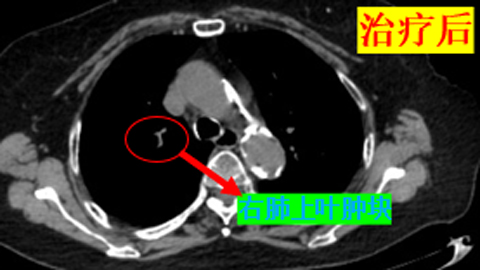

近日,一位83岁的小细胞肺癌患者在来凤县人民医院肿瘤科接受化疗治疗后,取得了令人瞩目的疗效,为无数患者带来了新的希望。据了解,患者是一位年逾八旬的老人,同时合并高血压,糖尿病等基层疾病。〔全文〕